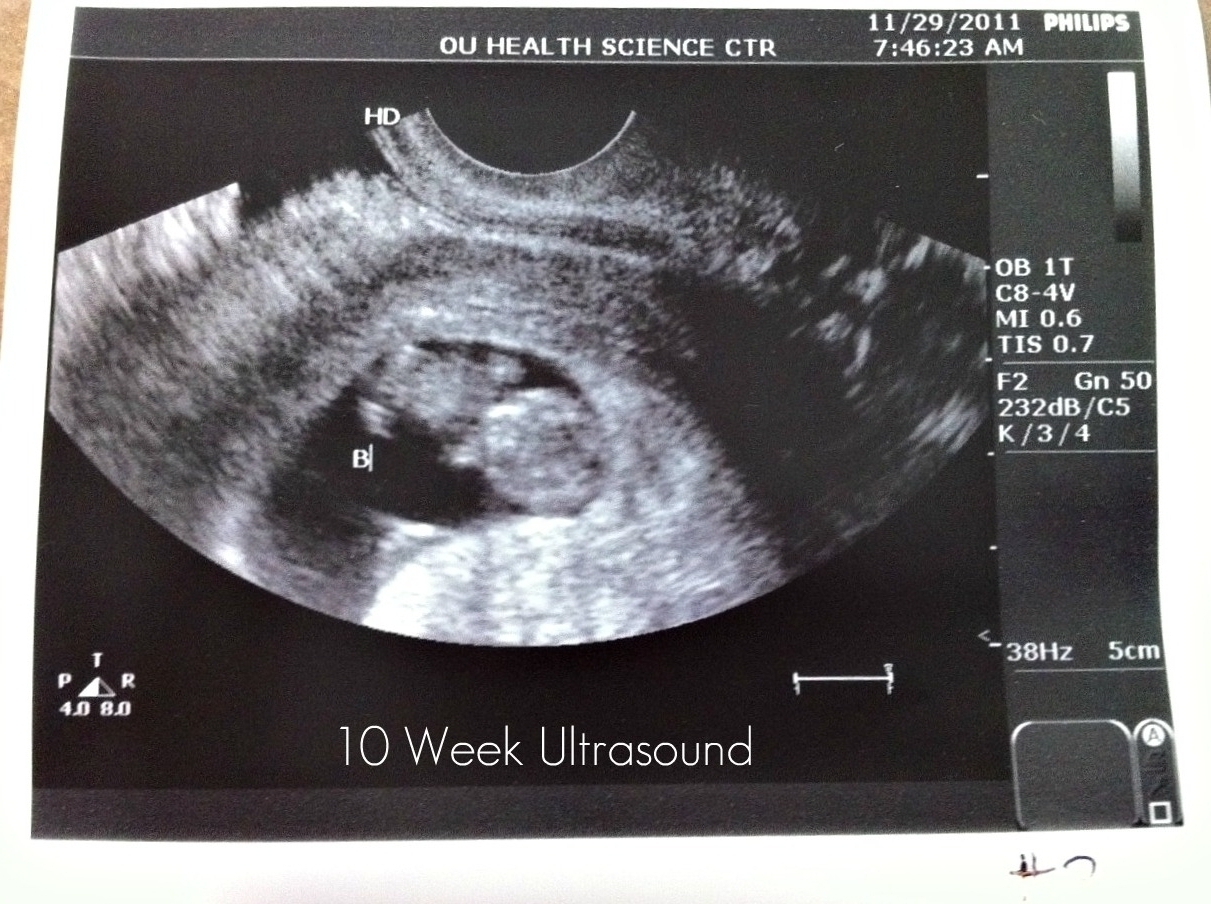

On Tuesday, November 29, I began my 10th week of pregnancy and had a third ultrasound with my specialist. It was my last appointment with them for this pregnancy. :( It's bittersweet to not have any more appointments with them because they are all so wonderful, but I have graduated on. :) I will begin seeing a regular OB/GYN in my 11th week. Here are some pics of my little ones. Baby A looks like a little gummie bear! ;) They were moving around SO much and kicking their little feet and waving their little hands. My doctor said they were feisty and healthy! One heartbeat was in the 170's and one was in the 180's. What miracles! It is just completely amazing that there are two lives growing inside of me.  I cannot even fully comprehend it!  God is faithful.